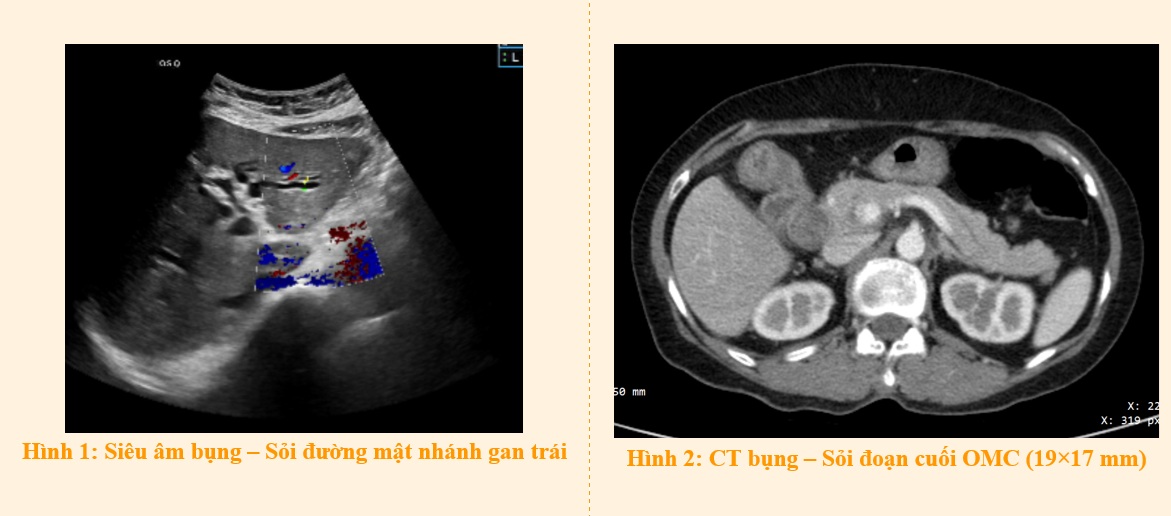

• Siêu âm bụng: Đường mật bị giãn to (cả trong và ngoài gan), có sỏi trong ống mật chủ.

• CT bụng có thuốc cản quang: Ống mật chủ giãn (20 mm), có nhiều viên sỏi ở đoạn cuối, viên lớn nhất khoảng 19 × 17 mm. Nhánh gan trái kích thước khoảng 8mm, lòng có vài viên sỏi kích thước khoảng 6 x 6 mm.

Kết hợp các dấu hiệu: sốt lạnh run + xét nghiệm viêm + hình ảnh sỏi gây tắc mật, bệnh nhân được chẩn đoán xác định: Viêm đường mật cấp do sỏi ống mật chủ và sỏi nhánh gan trái theo tiêu chuẩn Tokyo Guidelines 2018, cần can thiệp phẫu thuật.